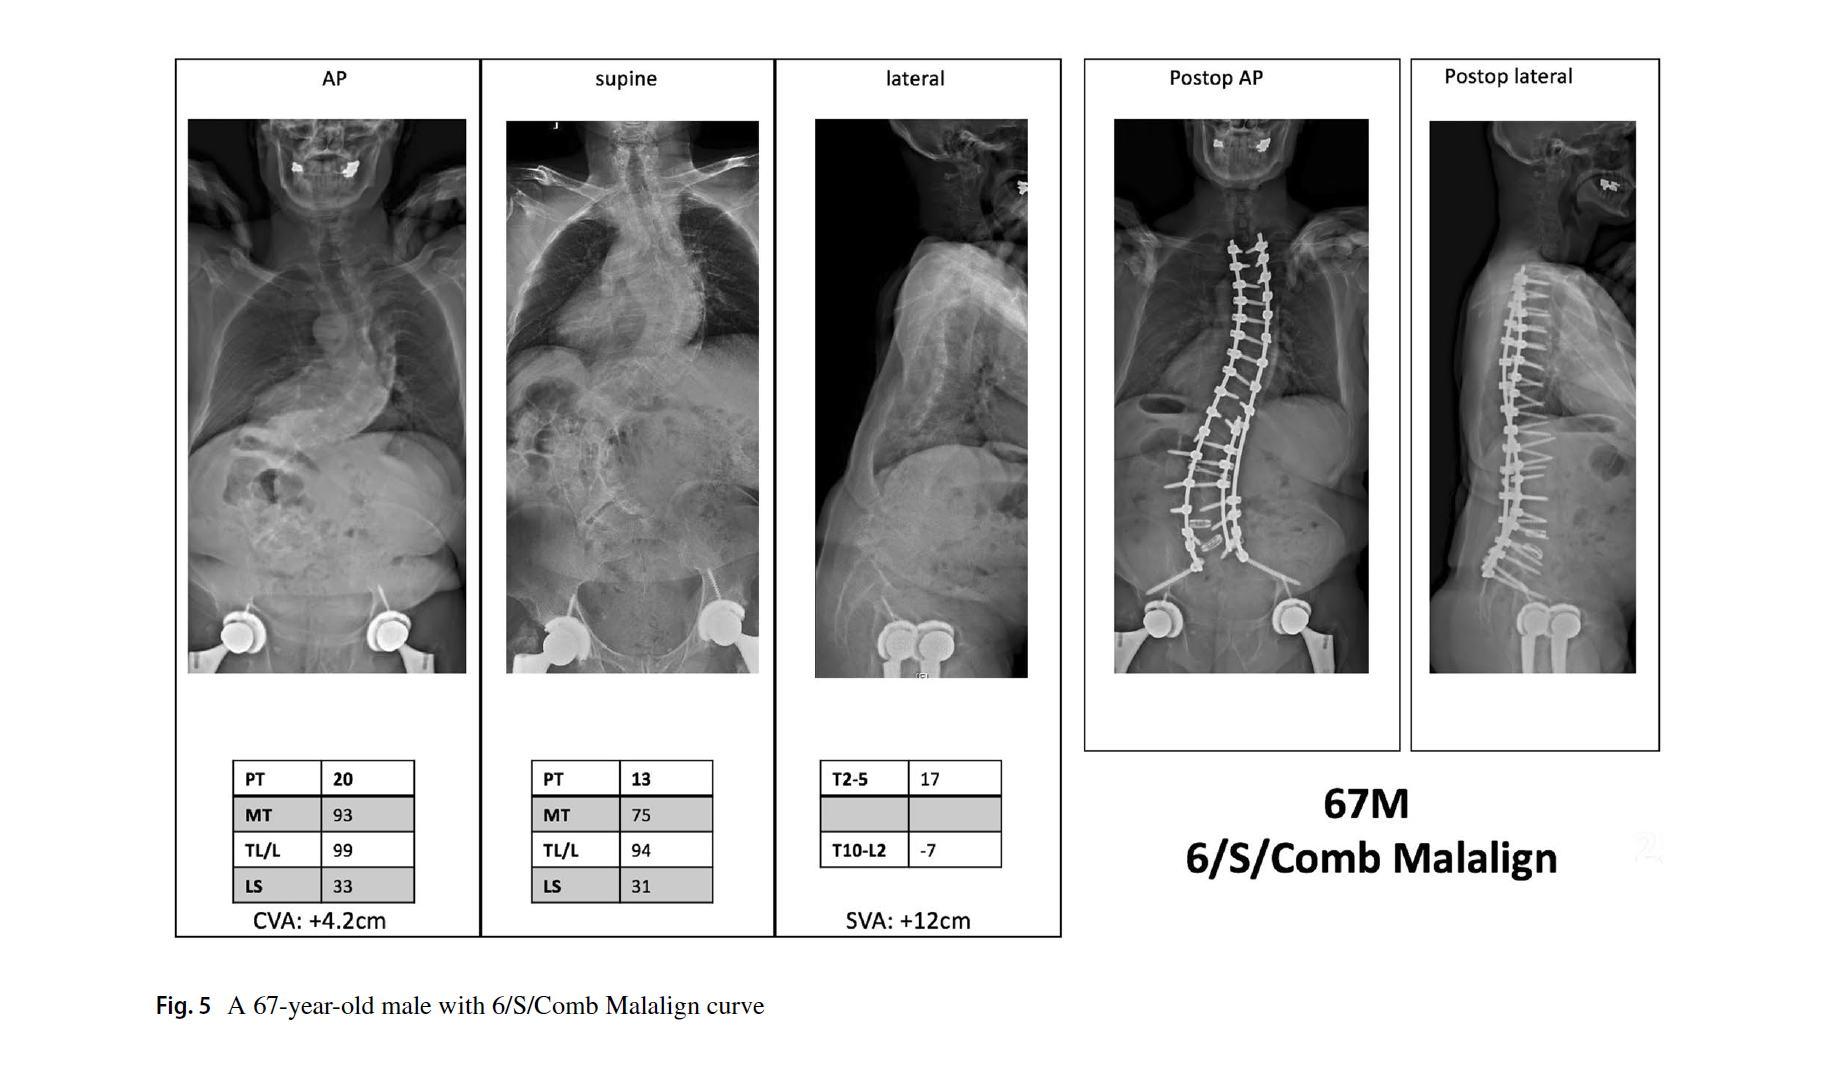

3. 脊柱平衡修正包括了冠状位、矢状位和冠矢合并的平衡状态。标准与SRS基本一致,冠状位失衡CVA≥40mm,矢状位失衡SVA≥40mm。排列组合,共有Aligned、Sag Malalign、Cor Malalign、or Comb Malalign 4种类型。如果脊柱失衡,需要按SRS标准矫正。